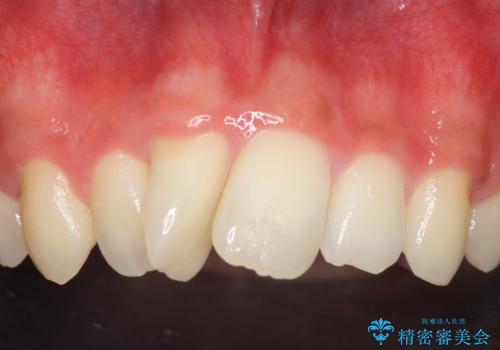

- 上顎前歯の歯並びが気になるが仕事が忙しく矯正治療は難しいため、セラミック矯正で綺麗にしたいといらっしゃった方の症例です。

左右の1番目の歯は傾きが大きいため、セラミッククラウンにするにあたり神経治療を行うことを御了承頂いた上で、前歯4本をオールセラミッククラウン(スペシャル)により補綴しました。